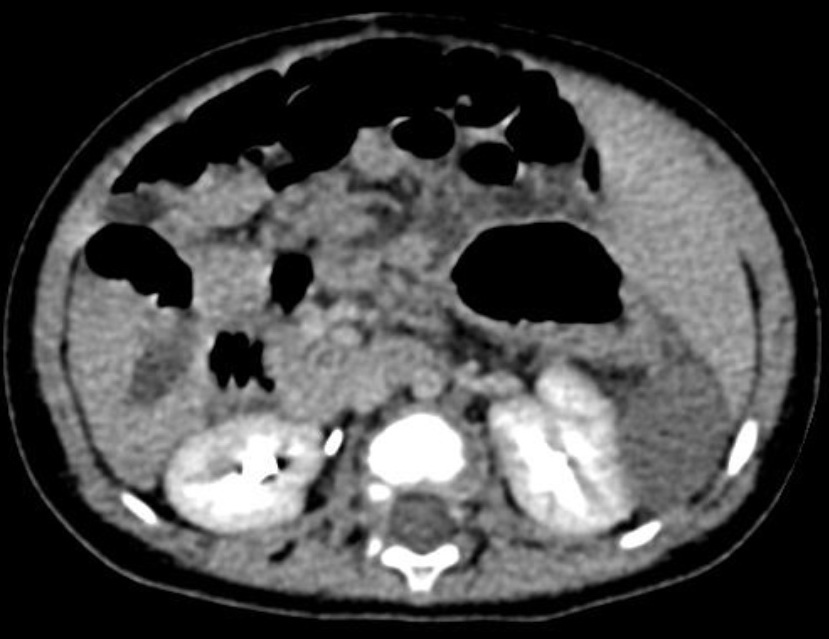

Компьютерная томография органов брюшной полости с внутривенным болюсным контрастированием.

Описание: Печень расположена срединно с преобладанием размеров левых отделов. Контуры ее ровные, четкие. Структура паренхимы однородная, плотность не изменена. Внутри- и внепеченочные желчные протоки не расширены. Желчный пузырь расположен срединно, перегиб в области тела, конкрементов нет.

Слева в проекции селезенки между задней поверхностью печени, желудком и левой почкой определяется овальное образование с четкими ровными контурами достаточно однородной структуры средней плотностью +48 ед. HU.

Поджелудочная железа нетипичной формы, расположена срединно, не увеличена, структура паренхимы однородная, плотность не изменена, контуры четкие. Парапанкреатическая клетчатка не изменена.

Надпочечники обычной формы и размеров, однородной структуры. Форма и размеры почек не изменены, контуры их ровные и четкие, структура однородная, плотность паренхимы - в пределах нормы. Чашечно-лоханочная система обеих почек не деформирована, не расширена, конкременты не обнаружены. Паранефральная клетчатка - без особенностей. Правая почка расположена выше левой верхний полюс её на уровне Th10, верхний полюс левой почки на уровне Th12. Свободной жидкости в брюшной полости и малом тазу нет. Мочевой пузырь умеренно выполнен. Патологических рентгенконтрастных теней не определяется. Патологических изменений скелета на исследуемом уровне не выявлено

После введения контрастного вещества: архитектоника сосудов не изменена. Верхняя брыжеечная артерия ориентирована вправо. Чревный ствол делится на две ветви, направленные влево, идущие к печени и желудку. Структур с типичным для селезёнки накоплением контрастного препарата не выявлено. Накопление контрастного препарата образованием не отмечено, к передней поверхности образования прилежат тонкие извитые сосуды, отходящие от брыжеечных. Дополнительных зон патологического накопления контрастного вещества не выявлено. Экскреторная функция почек по визуальной оценке сохранена. Мочеточники прослеживаются цистоидами на протяжении. Заключение: Состояние после эктомии добавочной селезенки. Аномалия расположения печени. Выявленное образование в левых отделах живота необходимо дифференцировать между перекрутом добавочной селезёнки, неопластическим процессом.

Рис 2 - Слева в проекции селезенки между задней поверхностью печени, желудком и левой почкой определяется овальное образование с четкими ровными контурами достаточно однородной структуры средней плотностью +48 ед. HU.